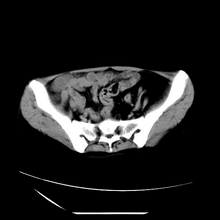

女性,41岁,发现左腹部包块3年,现行ct检查,检查前做过静脉肾盂造影。

脾脏增大,左肾后方脂肪增多,脊柱前方脂肪增多,左肾窦脂肪增多,左肾变形,双肾积水以左侧为著,左肾内侧及上方见环形软组织肿物影,内部低密度区,考虑1盆腹腔/腹膜后及左肾窦脂肪增多症2左肾内侧病灶可能为左肾上腺病灶,可能为脂肪增多的原凶

1)考虑左肾替代性脂肪瘤病;不排除左肾错构瘤。2)双肾积水。

腹膜后脂肪肉瘤累及左输尿管及左肾窦脂肪沉积,双肾积水,